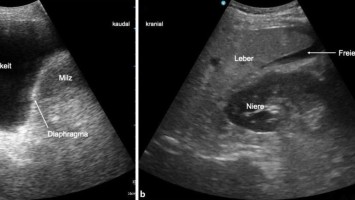

FAST bei kindlichem Bauchtrauma mit AST kombinieren?

Kann die Kombination aus FAST-Sonografie mit einem Aspartat-Aminotransferase-Test (AST) die CT-Diagnostik bei Kindern mit stumpfem Abdominaltrauma ersetzen? Ein indisches Forschungsteam hat sich auf die Suche nach einem sensitiven Score zur Erkennung von intraabdominalen Verletzungen gemacht.